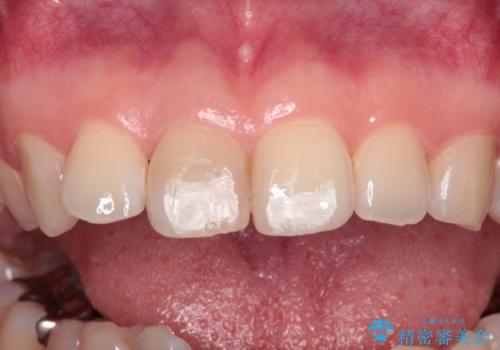

- 事故でぶつけて神経を取り除いた歯が変色したとのことで来院された患者様です。

処置直後は欠けた部分を詰めた材料で見た目に問題なかったそうですが、年々変色してきて、かなり目立つようになっていました。

根管治療された状態に大きな問題はなかったため、土台を植立し、オールセラミッククラウンにて補綴治療を行うこととしました。

オーダーメイドタイプのクラウンを選択されたため、周辺の歯と調和が取れる色合いとなるまで修正を繰り返しました。